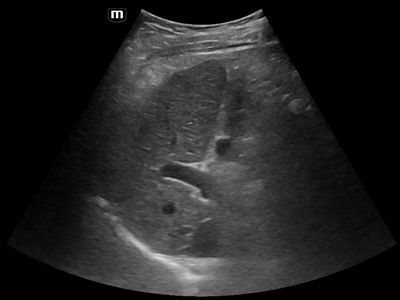

The patient underwent ultrasound examination for hepatocellular carcinoma screening, which yielded negative results (US-LR 1) (Figure 1, image from the screening protocol).

Figure 1: Image of the right hepatic lobe, with characteristic signs of cirrhosis.